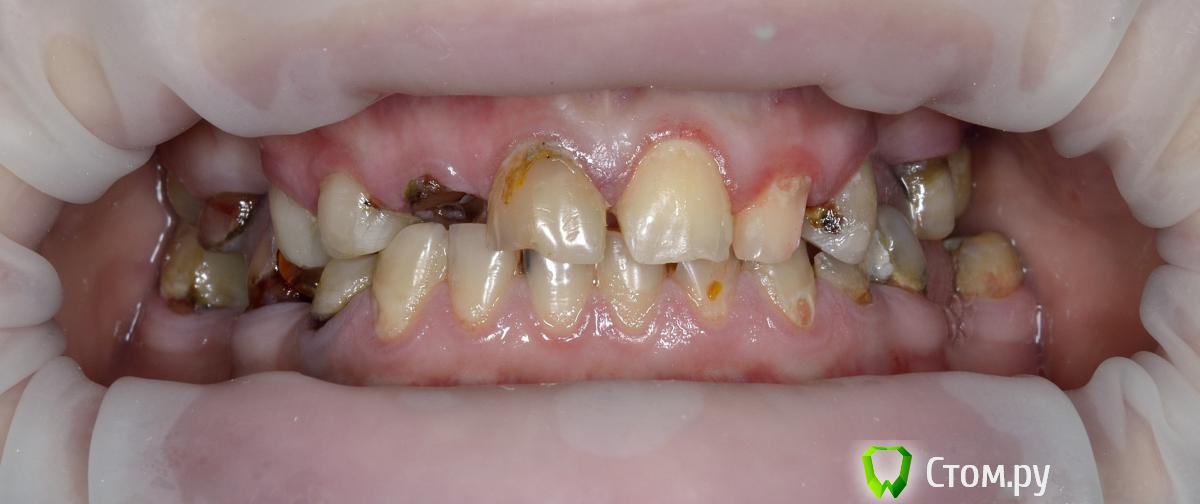

Vitremer Опубликовано 13 июля, 2014 Поделиться Опубликовано 13 июля, 2014 Здравствуйте! Пациентка 37 лет. Тотальное протезирование в/ч.Что делать:1.с уже ранее леченными и восстановлеными СВШ зубами 1.4 1.3 2.3 2.7 ? ( оставлять-менять на вкв...)2. корень 1.2 . ВКВ ? феррула почти нетПока такие вопросы. Ссылка на комментарий

Alex74 Опубликовано 13 июля, 2014 Поделиться Опубликовано 13 июля, 2014 (изменено) Давайте без сарказма. Пока она будет собирать на две челюсти-полетит все оставшееся. А импланты-совсем другой прайсНикакого сарказма. БОльшая часть зубов, судя по фото, очень сильно разрушена. Качественно их сделать будет стоить не дешевле имплантатов. Если перебирать их дорого, то тогда "более-менее" нормальные зубы - это резцы 11 21 22 и премоляр слева. Какие варианты бюджетные приходят в голову с 4 оставшимися во рту зубами? А ставить "на то что было, то и полюбила"...ну не знаю. Сколько оно простоит? Поэтому простое решение предложил - всё убрать и сделать ПСП. Изменено 13 июля, 2014 пользователем Alex74 Ссылка на комментарий

M@estro Опубликовано 13 июля, 2014 Поделиться Опубликовано 13 июля, 2014 Никакого сарказма. БОльшая часть зубов, судя по фото, очень сильно разрушена. Качественно их сделать будет стоить не дешевле имплантатов. Если перебирать их дорого, то тогда "более-менее" нормальные зубы - это резцы 11 21 22 и премоляр слева. Какие варианты бюджетные приходят в голову с 4 оставшимися во рту зубами? А ставить "на то что было, то и полюбила"...ну не знаю. Сколько оно простоит? Поэтому простое решение предложил - всё убрать и сделать ПСП. Себе бы так сделали ? Судя по исходной фото ? 1 Ссылка на комментарий